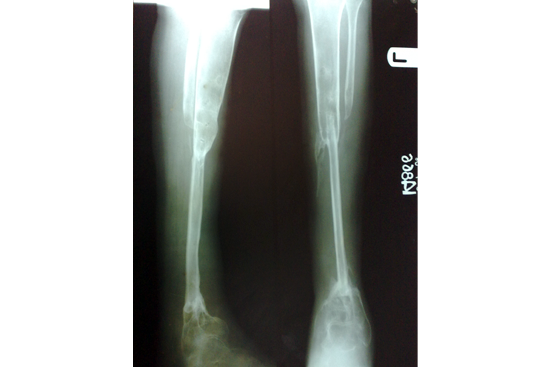

We have done Huntington technique by stage ilizarov procedure. Here is the diagrammatic representation of our method.